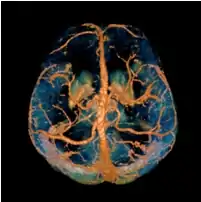

Quantitative Susceptibility Mapping (QSM) provides a novel contrast mechanism in Magnetic Resonance Imaging (MRI) different from traditional Susceptibility Weighted Imaging.[1][2][3][4][5] The voxel intensity in QSM is linearly proportional to the underlying tissue apparent magnetic susceptibility, which is useful for chemical identification and quantification of specific biomarkers including iron, calcium, gadolinium, and super paramagnetic iron oxide (SPIO) nano-particles. QSM utilizes phase images, solves the magnetic field to susceptibility source inverse problem, and generates a three-dimensional susceptibility distribution. Due to its quantitative nature and sensitivity to certain kinds of material, potential QSM applications include standardized quantitative stratification of cerebral microbleeds and neurodegenerative disease, accurate gadolinium quantification in contrast enhanced MRI, and direct monitoring of targeted theranostic drug biodistribution in nanomedicine.

COSMOS assumes a model-free susceptibility distribution and keeps full fidelity to the measured data. This method has been validated extensively in in vitro, ex vivo and phantom experiments. Quantitative susceptibility maps obtained from in vivo human brain imaging also showed high degree of agreement with previous knowledge about brain anatomy. Three orientations are generally required for COSMOS, limiting the practicality for clinical applications. However, it may serve as a reference standard when available for calibrating other techniques.